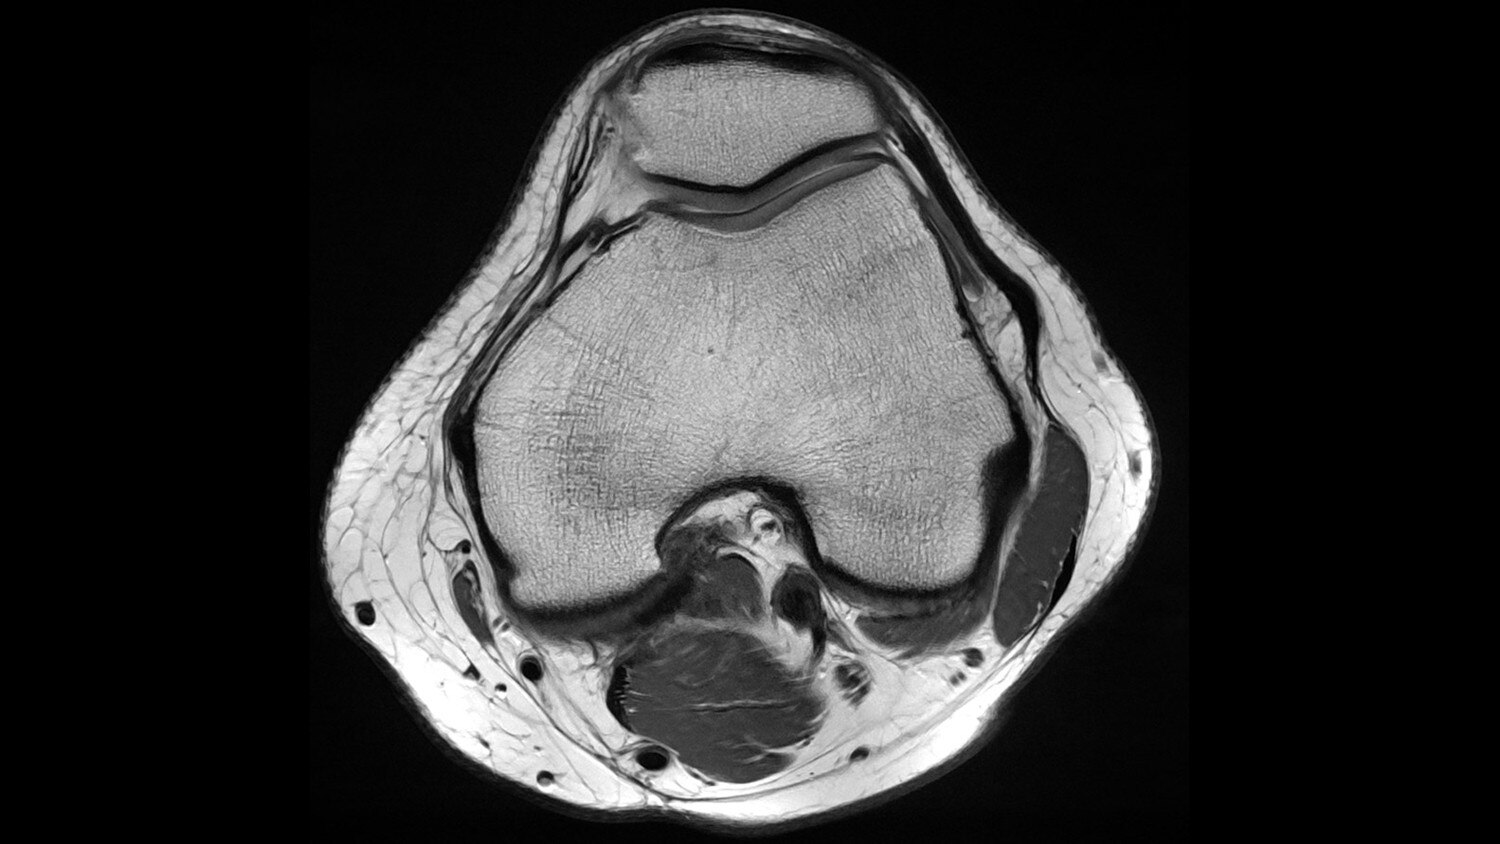

Its full 3.0T magnet and 70 cm bore work together to generate extraordinary image quality without compromises. The result for clinicians is new levels of diagnostic performance.

A large usable field of view is needed to properly image off-center anatomy such as a shoulder or hip. So the Discovery* MR750w features a 70 cm flared, open bore design with a large 50 x 50 x 50 cm field of view.

Gradients and RF body coils are water and air-cooled for optimum duty-cycle performance, short repetition time (TR) and echo time (TE), producing sharp and clear images.

Intuitive applications help clinicians utilize the full potential of 3.0T MR imaging.